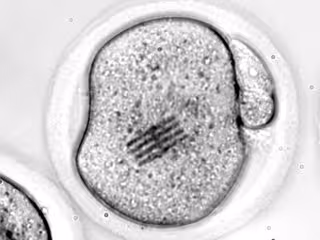

Un grupo de investigadores de diversos hospitales y centros de reproducción asistida, públicos y privados, de Dinamarca, Suecia y España, entre los que se incluye el jefe del Servicio de Medicina de la Reproducción de Dexeus Mujer, Nikolaos Polyzos, ha demostrado que congelar los embriones y transferirlos en diferido no afecta al éxito de los tratamientos de reproducción

En los últimos años, la práctica de transferir embriones previamente congelados en tratamientos de reproducción asistida ha ido creciendo de forma progresiva, gracias a las mejoras introducidas en el laboratorio, como la vitrificación (un proceso que permite congelar material biológico de forma mucho más rápida y segura), y la optimización de los cultivos que facilitan el desarrollo del embrión en el incubador.

En este nuevo estudio, publicado en la revista 'The British Medical Journal', participaron un total de 460 mujeres de entre 18 y 39 años, con ciclos menstruales regulares que fueron incluidas en el estudio durante el inicio de su primero, segundo o tercer ciclo de Fecundación in vitro o ICSI (microinyección intracitoplasmática de espermatozoides).